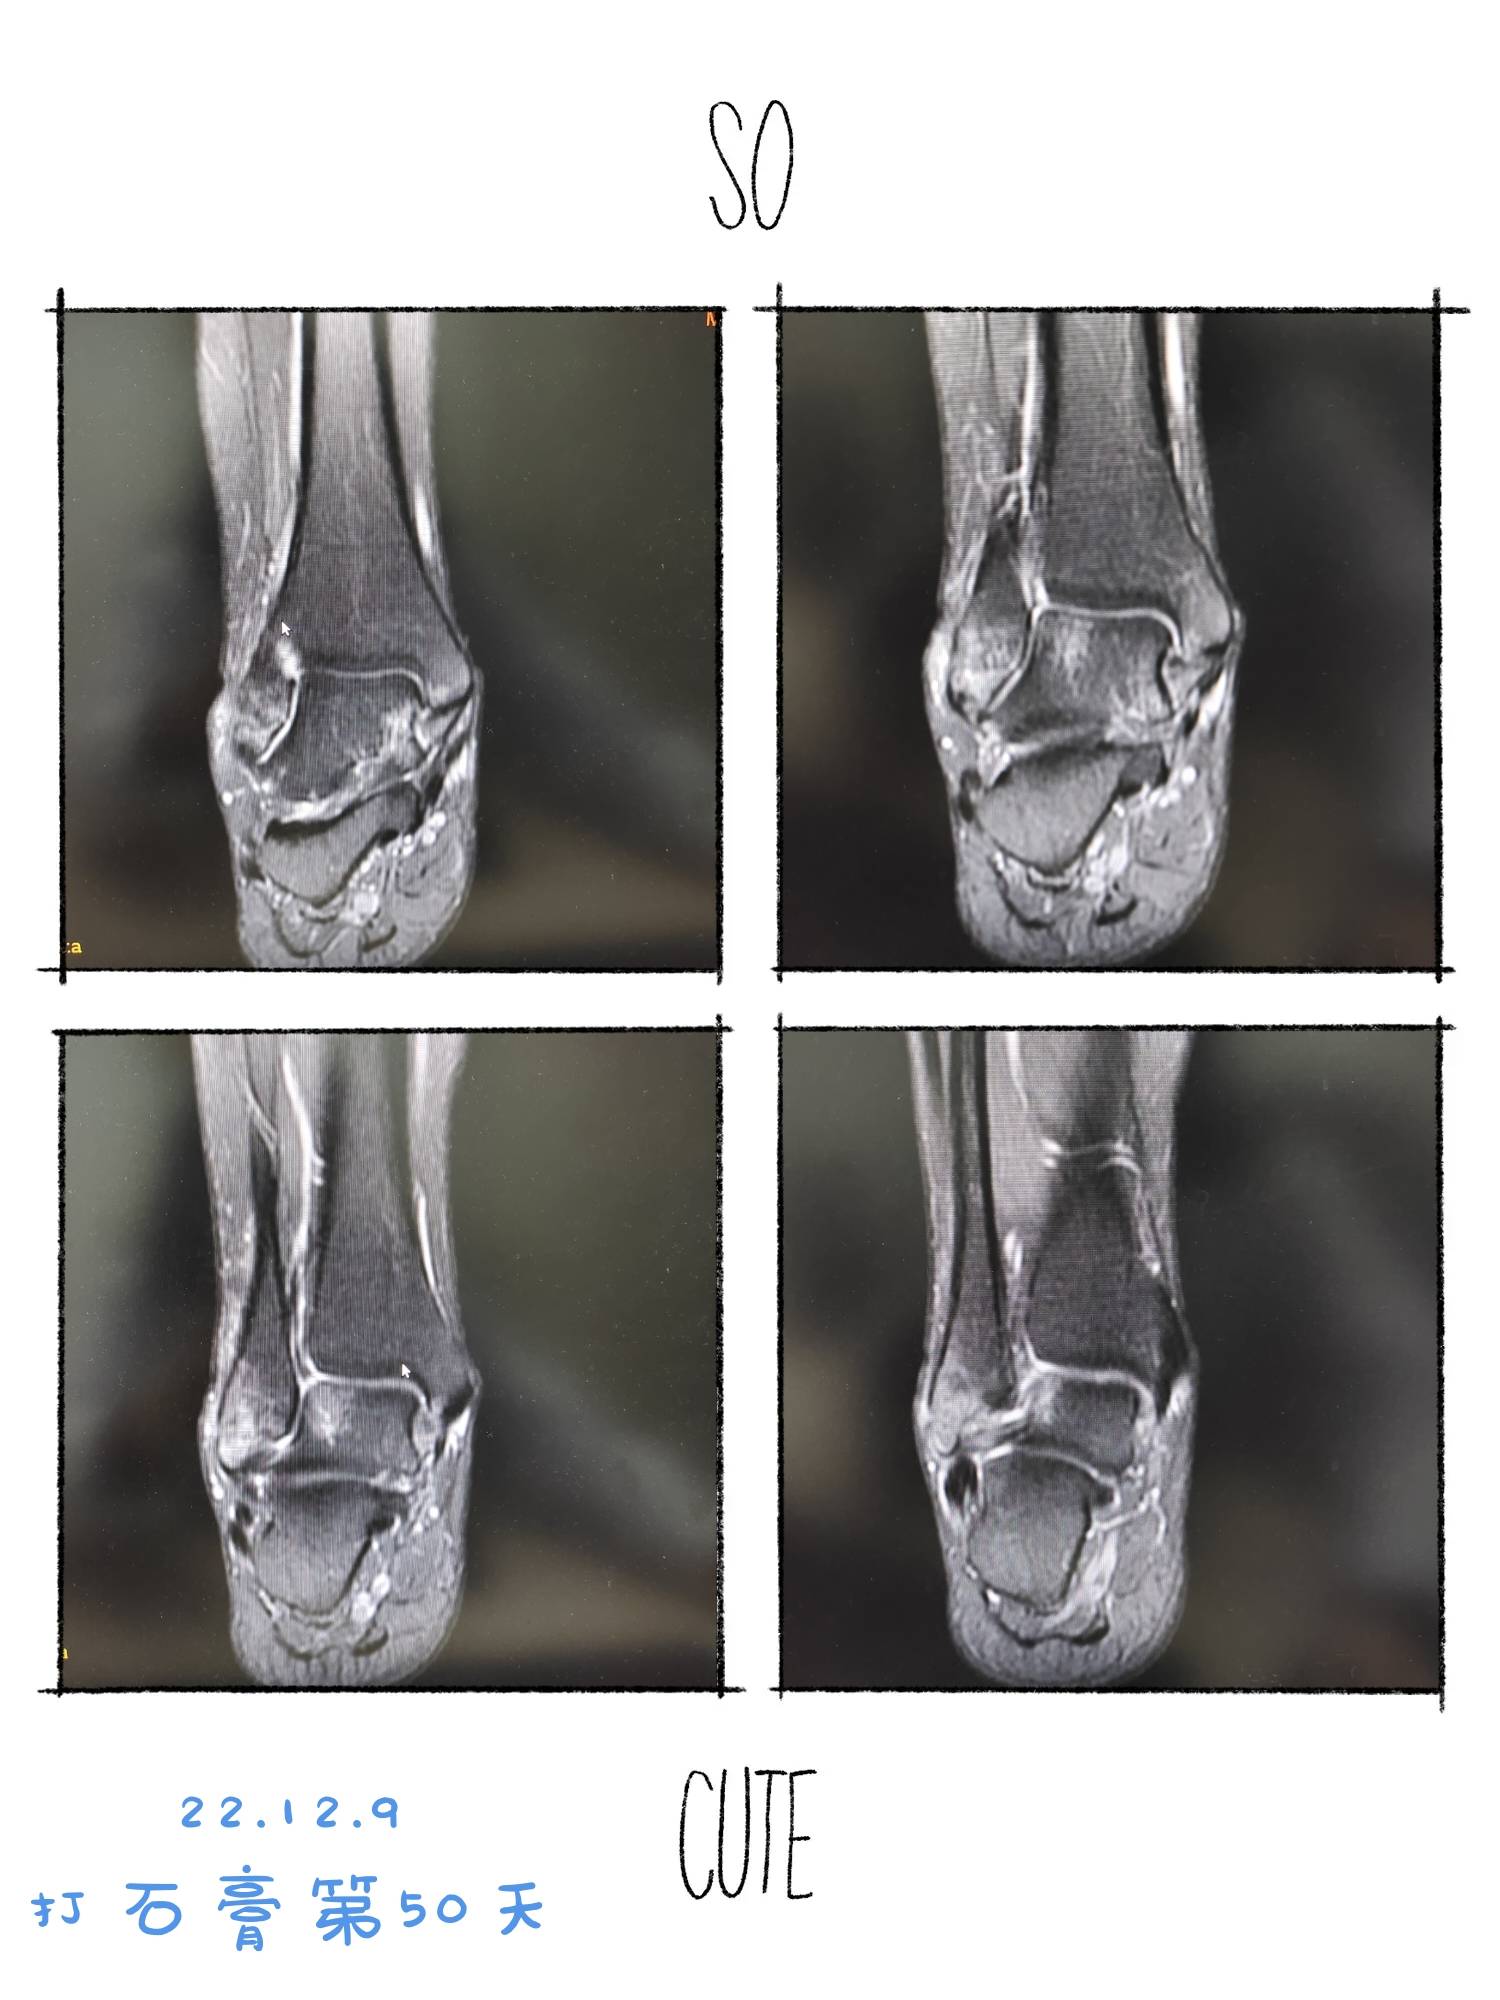

22.12.9拆石膏咯。不必拄拐。但是医生嘱咐一定要“慢慢走”。至少三个月以后才能跑跑跳跳。但是能拆石膏已经很开心了。我终于可以穿秋裤和棉毛裤了。